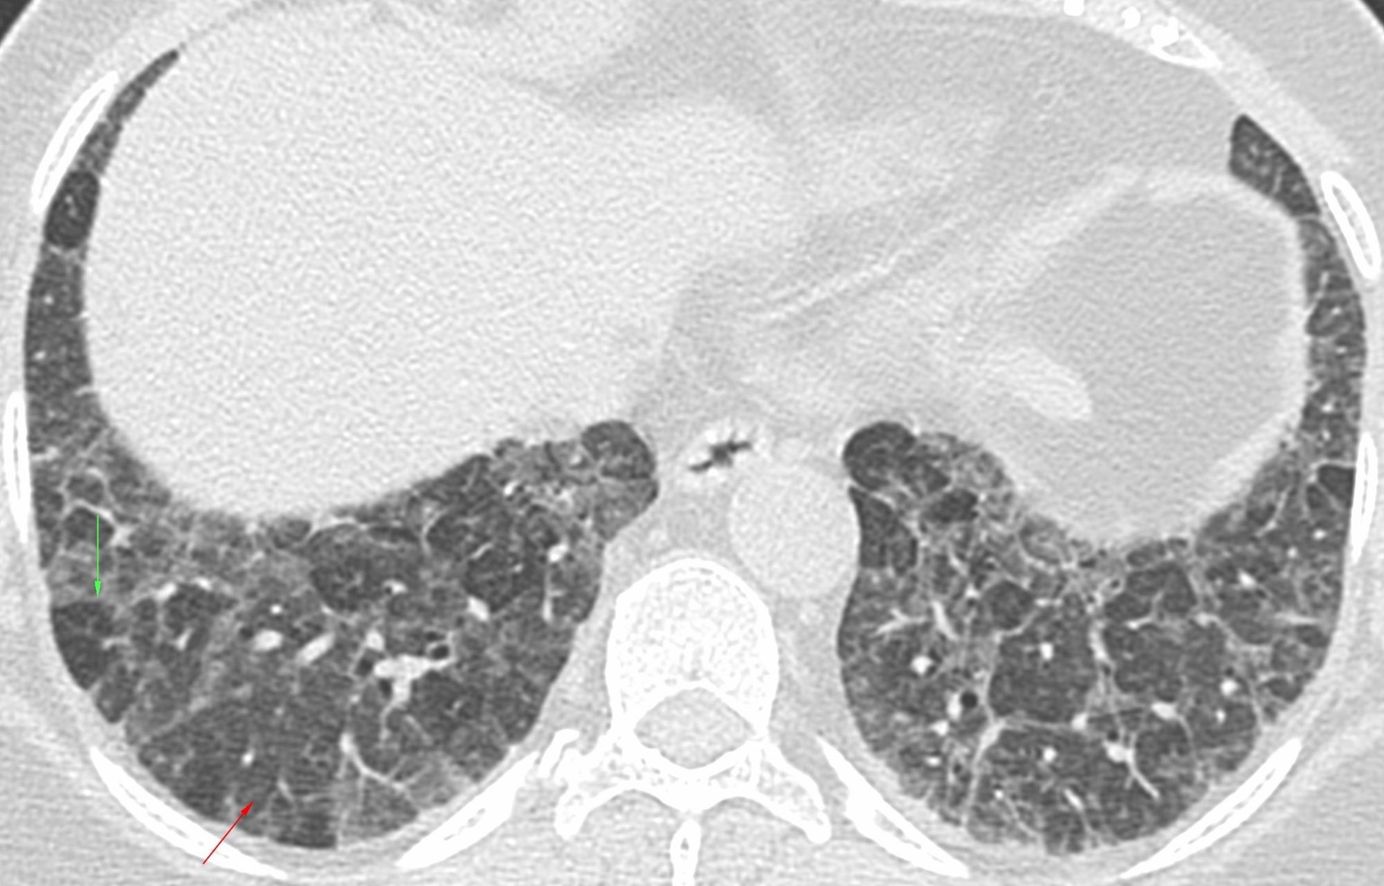

Case 17: Tuberculosis and Hemoptysis - Dense and Soft Centrilobular Nodules Together Members Public

17-years old with tuberculosis and hemoptysis - dense and soft centrilobular nodules together.